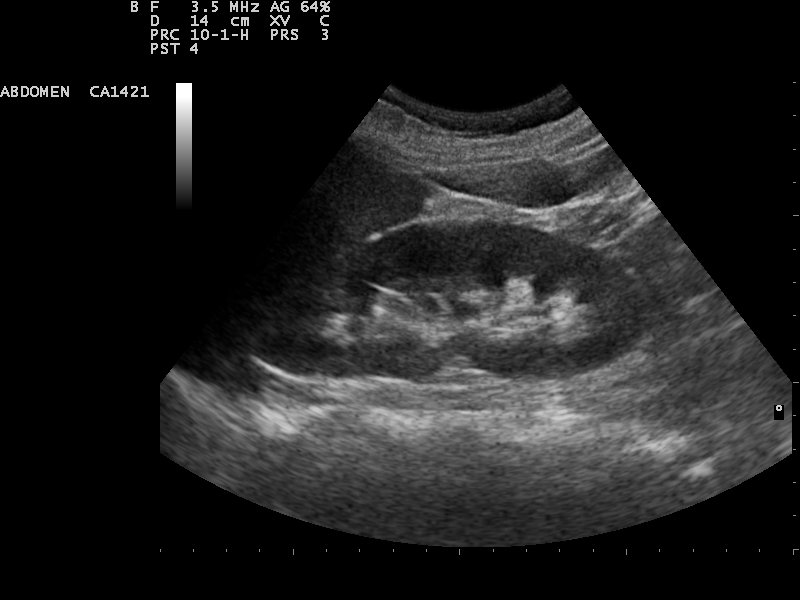

2) Consider the following image of a kidney using sound waves. The sound waves are produced at the top of the image and travel downwards. As they are reflected back they are detected at the top. How much sound is reflected back and when it arrived (much like problem 1) is used to create the image.

- From "top to bottom" on the picture a kidney is about 5 cm "wide". How much longer will it take sound to get back to the detector from the "bottom" of the kidney compared to the "top"?